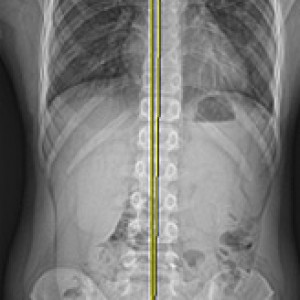

검사부터 다른 당당

“당당은 뼈만 보지 않습니다.”

근육과 근막의 정렬을 함께 진단하며, 풀 스파인 촬영을 통해 머리부터 모든 고관절, 발의 정렬까지 함께 파악하여 개개인에 맞는 전신 치료법을 설계합니다.

전신 엑스레이 검사